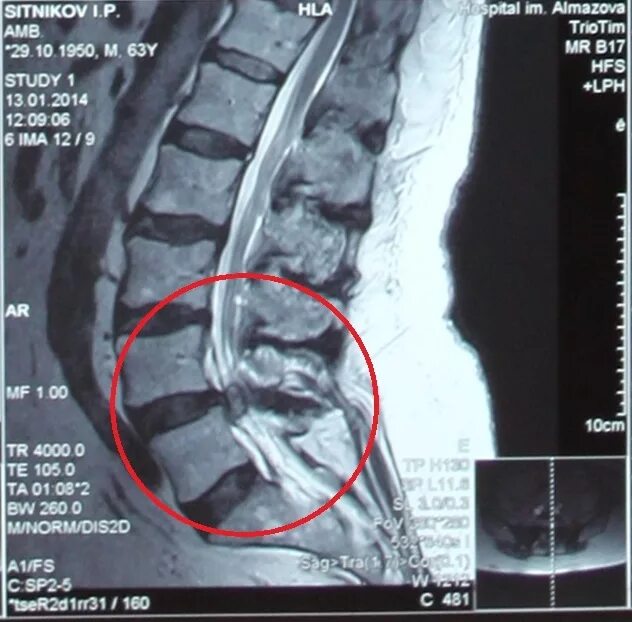

Экструзия l5 s1 диска что это такое